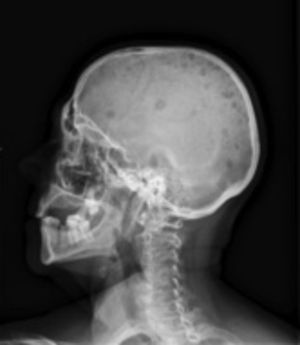

Radiología. La radiografía de cráneo muestra lesiones líticas (fig. 1). La radiografía anteroposterior y lateral de columna dorsolumbar: acuñamiento vertebrales en D7 y D11 con cambios degenerativos. Radiografía de parrilla costal anteroposterior izquierda: presencia de un patrón permeativo difuso en costillas, escápula y húmero (fig. 2).